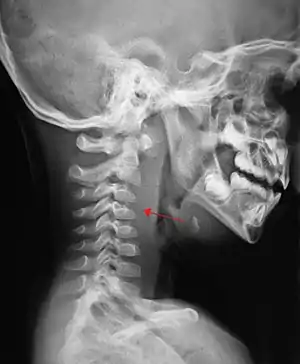

A lateral cervical spine x-ray demonstrating prevertebral soft tissue swelling (marked by the arrow) as seen in a person with a retropharyngeal abscess. | |

X-ray of the neck often (80% of the time) shows swelling of the retropharyngeal space in affected individuals. If the retropharyngeal space is more than half of the size of the C2 vertebra, it may indicate retropharyngeal abscess.[5]